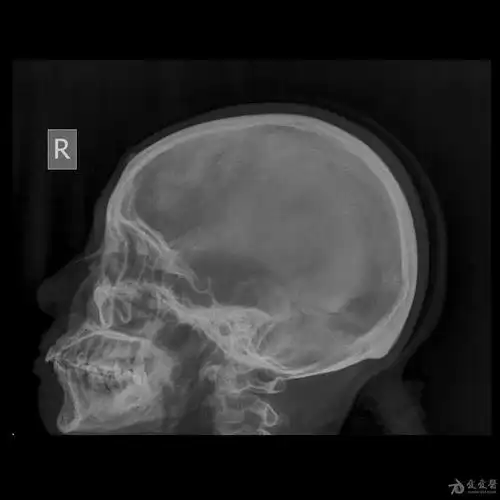

头颅x片 ~ 额骨高密度影